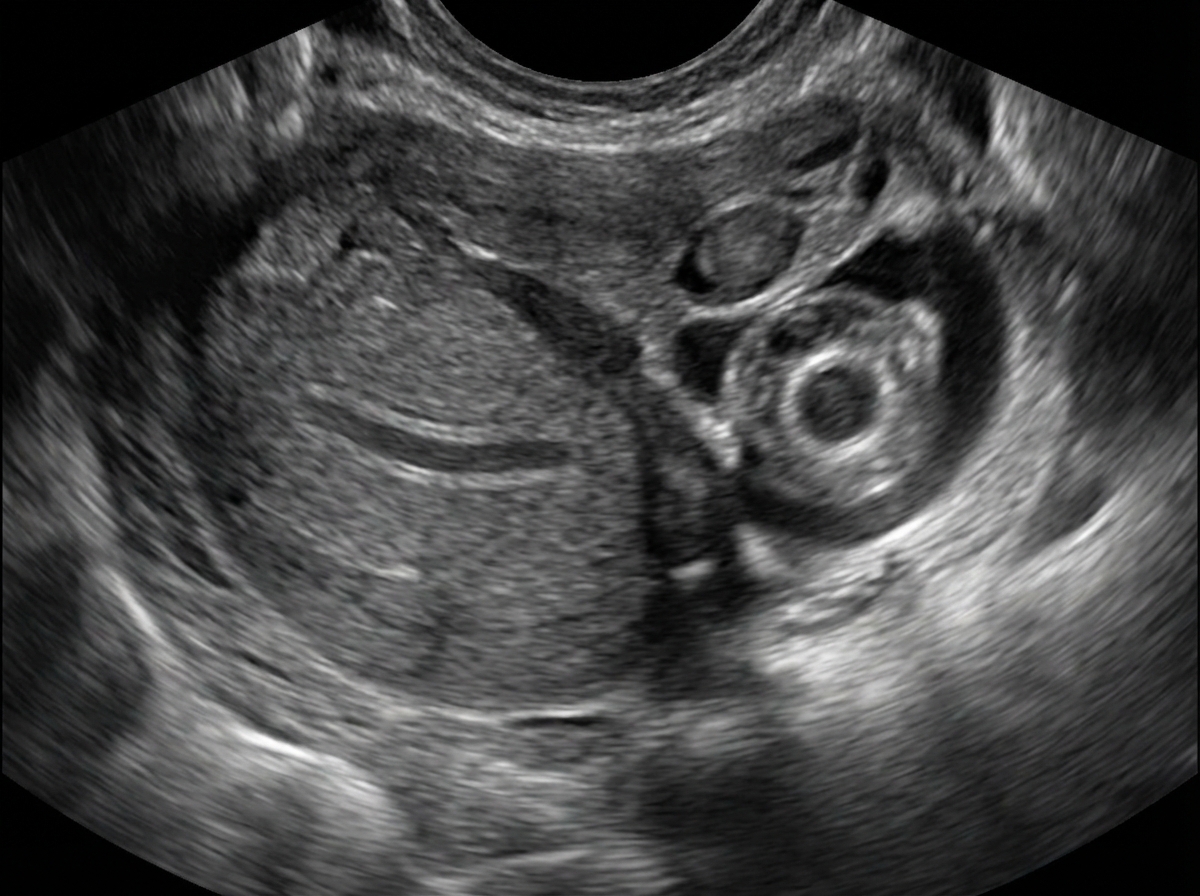

What does the following ultrasound show?

Explanation: ***Ectopic pregnancy*** - Classic **transvaginal ultrasound** findings include the **adnexal ring sign** (hyperechoic ring in the fallopian tube) and an **empty uterine cavity** despite positive pregnancy test. - Often shows **free fluid** in the **pouch of Douglas** indicating potential tubal rupture or bleeding. *Normal pregnancy* - Shows a **gestational sac** within the **uterine cavity** with appropriate size for gestational age. - **Fetal pole** and **cardiac activity** are visible in viable intrauterine pregnancies after 6-7 weeks. *Hydatidiform mole* - Characteristic **"snowstorm appearance"** with multiple **cystic spaces** and **echogenic material** filling the uterine cavity. - Absence of **normal fetal structures** and markedly elevated **β-hCG levels** compared to gestational age. *Ovarian cyst* - Appears as a **simple fluid-filled structure** with **thin walls** and **anechoic contents** in the ovary. - **Uterine cavity** would show normal intrauterine pregnancy if patient is pregnant, not the empty uterus seen in ectopic pregnancy.